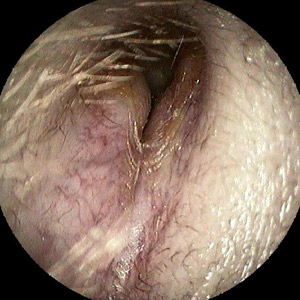

Gehörgangsexostose linkes Ohr